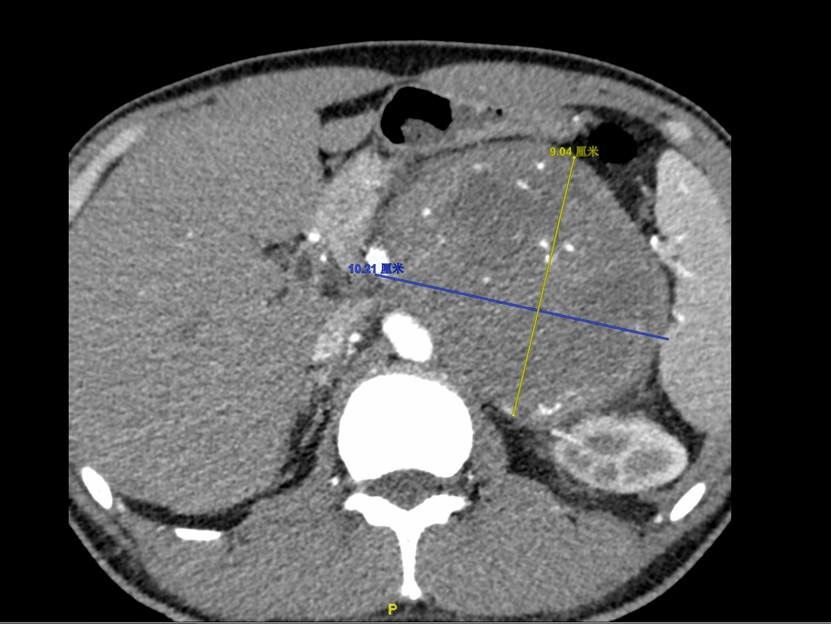

患者影像检查结果

任明华介绍,正常的肾上腺长为4-6cm,宽为2-30cm,厚度为0.3-0.6cm,位于腹膜后膈肾之间,包于肾周筋膜和脂肪囊内,左侧肾上腺隔着腹膜与脾脏相望,血供极丰富。而从术前检查结果来看,该患者左侧肾上腺肿物竟达到10*9cm之大,并且与周围脏器血管关系密切,与其前方隔着腹膜相望的胰腺明显受压移位,其周围脏器的滋养血管及回流静脉也难逃“压迫”的命运,包括脾动脉、左肾动脉和左肾静脉。